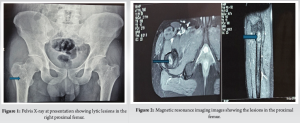

On evaluation of the swelling of the proximal thigh, X-ray of the pelvis with hip revealed a lytic lesion in the right proximal femur (Fig. 1). Further imaging with magnetic resonance imaging (MRI) revealed lytic lesions in right proximal femur and right pubic bone, with a heterogeneous hypoechoic collection in the thigh extending into the femur (Fig. 2). X-ray of the chest revealed a lytic lesion in the right 9th rib (Fig. 3). A computed tomography (CT) scan of the thorax revealed an expansile lytic lesion in 9th rib on the right side with a soft tissue collection, along with a subpleural cavitary nodule in the left lower lobe posterior basal segment. Routine sputum culture yielded no growth. Sputum acid-fast staining and culture for TB were also negative. He was hence diagnosed as a case of clinically diagnosed TB and was started on anti-tubercular therapy from elsewhere. However, even after 2 months of anti-tubercular therapy, the patient reported no improvement in symptoms and presented to our hospital.

On repeat imaging, the lesions in the proximal thigh and the chest wall were noted to have increased in size. Repeat blood investigations yielded a similar picture and repeat culture of the sputum with investigations for TB with acid-fast staining, culture, cartridge-based nucleic acid amplification test, and QuantiFERON gold TB test were negative and ruled out a tuberculous infection. We aspirated fluid from the soft tissue lesion in the right proximal femur and the right posterior chest wall for analysis, with a fine-needle aspiration cytology (FNAC) of the affected rib, cytology, extended culture for atypical organisms, and a fungal culture were sent. Although other investigations were unyielding, the fungal culture from the thigh swelling turned out to be positive for C. neoformans. A fungal culture from the collection on the chest wall and a blood culture also yielded C. neoformans. Cerebrospinal fluid (CSF) cultures were negative. Further, as Cryptococcus usually occurs in those exposed to birds, further questioning revealed exposure to pigeons at his home. Hence, he was diagnosed as a case of disseminated cryptococcosis and was started on lipophilic amphotericin B and fluconazole with serial monitoring of renal parameters. The anti-tubercular therapy was stopped. Amphotericin B was given at a dose of 0.8 mg/kg infusion over 2–4 h in 5% dextrose daily and oral fluconazole 400 mg once daily was given for 1 month. The patient became symptomatically better, and his general condition improved significantly. After 1 month of intravenous therapy, he was started on the consolidation phase with oral fluconazole 400 mg once daily for a total 8 weeks, followed by the maintenance phase with fluconazole 200 mg once daily. As cryptococcosis occurs predominantly in immunocompromised individuals, and as his HIV enzyme-linked immunosorbent assay was negative, further search into immunodeficiency was done. A clinical exome sequencing, lymphocyte subset analysis, immunoglobin profile, native T cell assay and a nitroblue tetrazolium test for immune function. The results revealed an isolated CD4 lymphocytopenia with a CD4 count of 75 (<14%) (Table 1). As he is also at risk of infection with Pneumocystis jirovecii pneumonia due to his immunodeficiency, he was also started on trimethoprim-sulfamethoxazole prophylaxis. The patient is currently at 1-year follow-up. A repeat MRI of the pelvis revealed consolidation of the lesion in the proximal femur and pubic bone. CT of the thorax revealed complete resolution of the lesions in the chest. Chest X-ray (Fig. 4) and X-ray pelvis (Fig. 5) at 1-year follow-up revealed consolidation of the lytic lesions. ESR and CRP have also stayed consistently normalized at 1-year follow-up, and the patient has been symptom free after discharge.